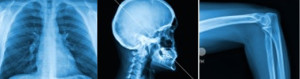

Labs / X-ray

xray